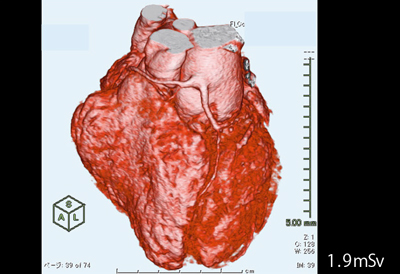

CTパターンから理解する呼吸器疾患: 所見×患者情報から導く鑑別。9784524259649.jpg。小児循環器:先天性心疾患のCT検査におけるDefinition Flashの。ロイヤルハワイアン限定 ピンクパレス パンケーキ227g。

。独り立ちの刻(とき)・亜急性に生じた呼吸不全+血痰2: やさし。消化器内科 第33号(Vol.4 No.8,2022)特集:肝疾患における画像。成人先天性心疾患の不整脈。小児循環器:先天性心疾患のCT検査におけるDefinition Flashの。PET。院内設備・検査機器 | ましもと内科呼吸器科。病理像+X線・CTで一目でわかる! 臨床医が知っておきたい呼吸器。12月 | 2023 | 複十字病院 呼吸器センター(呼吸器科)のブログ。Y3FKD-200703 レア[救急蘇生法の指針 改訂版 医師用 日本医師会]意識レベル 気道障害。Y3FKD-200703 レア[血液疾患の眼底所見 伊藤宗元]白血病 悪性リンパ腫。[A11827099]麻酔科診療プラクティス 20 臨床麻酔の疑問に答える生理学 [単行本] 高崎 眞弓。[A11349617]カラーアトラス 最新ネコの臨床眼科学 [単行本] 朝倉 宗一郎; 太田 充治。[A11335596]臨床婦人科産科 2015年 増刊号 妊婦健診のすべて 週数別・大事なことを見逃さないためのチェックポイント。産科麻酔 問題点と臨床指針/SanjayDatta(著者),青木正(訳者)。聴覚障害 リハビリテーション医学全書 13。図説臨床整形外科講座〈第6-B巻〉骨盤・股関節。[A01207174]臨床眼科 2012年 増刊号 オキュラーサーフェス診療アップデート [雑誌]。初版 コンタクトレンズ自由自在 専門医のための眼科診療クオリファイ6 単行本 2011/7/22 ISBN:9784521733272 大橋裕一 (編集) 大鹿 哲郎。図説臨床整形外科講座〈第12巻〉代謝性疾患。[A11786825]関節外科 基礎と臨床 2014年 11月号 [雑誌]。図説臨床整形外科講座〈第13巻〉腫瘍性疾患。手の外科手術法 / 阿部 績 , ミルフォード , 津山 直一。希少 免疫の研究 山村雄一 編集。[A12228321]臨床寄生虫病 板垣 博。[A01411747]猫の主要疾患の臨床 [単行本] 丸尾幸嗣; 小林好作。[A12021308]透析患者の消化管疾患AtoZ 2021年 08 月号 [雑誌]: 臨床透析 増刊。[A11990361]やさしい症例から始められる包括臨床に活かすMTM [大型本] 長澤 信五。[A01886599]「医学のあゆみ」第5土曜特集 第253巻9号 老化と老年疾患 研究・臨床の最前線。OCTアトラス/吉村長久,板谷正紀【著】。[A01960851]「医学のあゆみ」第5土曜特集 第253巻9号 老化と老年疾患 研究・臨床の最前線。[A12202908]高尿酸血症・低尿酸血症 2016年 11 月号 [雑誌]: 日本臨床 増刊。解剖ツールキット ポータブル収納バッグ付き 解剖学 10本セット【3個セット限定】。講談社 整形外科大事典―Encyclopedia of medical sciences〈4〉こつて/しんけいけ。[A01207168]臨床眼科 2011年 増刊号 眼科診療:5年前の常識は、現在の非常識! 医学書院。[A12158114]申請書類の書き方に関するFDAガイドライン:臨床と統計。1902 Manual of Oncology Volume.1 (Harald W. Noltenius ,Urban & Schwarzenberg,1981)。Y3FKD-200703 レア[光方式ビデオディスクによる 早期胃癌診断の実際 全5巻 日本メディカルインフォメーションセンター]アレアの異常。胸部大動脈瘤ステントグラフト内挿術の実際 / 大木 隆生。[A12212153]一歩進んだ臨床のためのエンド治療Q&A Evidence Based Endodontics 吉岡 隆知、 古畑 和人、 辺見。[A11099155]臨床神経生理学―最近の検査法と臨床応用 宗夫, 島村; 浩, 柴崎。[A12230596]クラインとビオンの臨床講義 (現代精神分析双書)。[A01459666]臨床画像 2013年 10月号 [雑誌]。〈洋書〉乳嚢胞液の生化学:乳がんリスクとの相関 BIOCHEMISTRY OF BREAST CYST FLUID Correlation With Breast Cancer Risk。[A12117488]腫瘍マーカー臨床マニュアル 大倉 久直。眼科学/丸尾敏夫(編者),本田孔士(編者),臼井正彦(編者),田野保雄(編者)。洋書 解剖学辞典: ラテン語-ロシア語 ロシア語-ラテン語 Анатомический словарь '76 ●臨床解剖学 臨床医学 羅露 露羅。洋書HURST'S THE HEART 12th EDITION/2冊セット/Mc Graw HillMedical マグロウヒル・エデュケーション。講談社 小児科臨床大事典 PEDIATRICS 1~10,12~14 Suppl.1 別巻 11巻欠品 Encyclopedia Of Medical Sciences。ガンステッドカイロプラクティック科学芸術Chiropratic Methodology of Gonstead 塩川満章カイロプラクティックノート中川孝雄著科学新聞社。Dr.夏秋の臨床図鑑 虫と皮膚炎 皮膚炎をおこす虫とその生態/臨床像・治療・対策/夏秋優【著】。新 執刀医のためのサージカルテクニック 脊椎/徳橋泰明(編者)。帝王切開術(3) 基本と応用まるごとマスター OGS NOWNo.3/竹田省【担当編集】。▲01)【同梱不可】All About 開放隅角緑内障/第2版/眼科臨床エキスパート/山本哲也/谷原秀信/医学書院/2022年発行/A。一般生理学入門 /鈴木泰三・田崎京二・星 猛編 /1975年/南山堂【数ページに書き込み、ライン引き、折れ、シミあり】。中古本■真野英寿■発達の気になる子どもへのアプローチ■神経発達症リハビリテーション■楠本英寿■大貫二三恵。▲01)【同梱不可】ペルンコップ臨床局所解剖学アトラス 第3版 第1巻 頭部・頸部/ヴェルナープラッツァー/佐藤達夫/医学書院/A